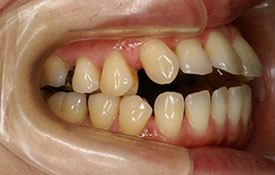

インビザラインの治療例:CASE-2

| プロフィール | 15歳 男性 |

| 所見 | アメリカから転院されて来られた方です。 インビザラインで上下顎の矯正治療を開始し下顎はアメリカで終了しており、上顎のみ治療の後期を担当しました。 アイライナーの装着は、1日平均22時間ほどでした。 |